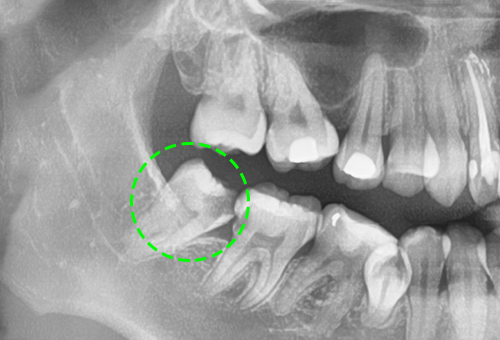

• 매복된 사랑니

아직 자라지 않았거나, 머리 부분만 자란 사랑니는 간혹 치아를 둘러싸고 있는 치아주머니에 물이 차

염증반응을 일으키기 쉽기 때문에 눈에 보이지 않더라도 발치하는 것이 좋습니다.